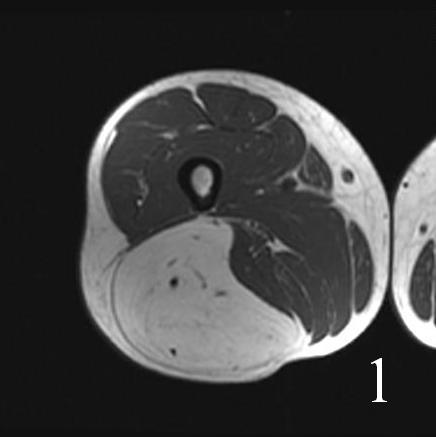

• High signal intensity similar to fat on T1W and T2W (Fig. 1 and 2)

• T1W shows areas of low signal intensity between that of fat skeletal muscle

• On fat suppression sequences show incomplete fat suppression.

Fig. 1-2 MRI of lower extremity hibernoma (Fig. 1 and Fig. 2) shows similar signal intensity to subcutaneous fat fat on different sequences.